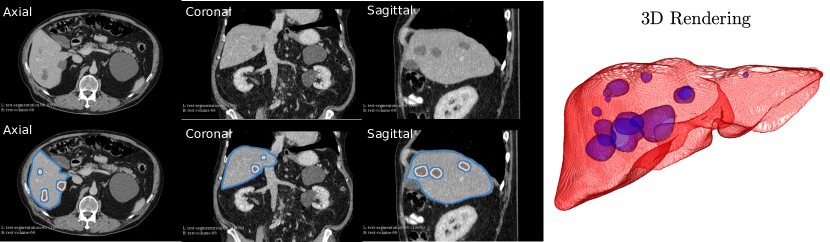

Appendix B Liver Tumor Segmentation Challenge

We show 9 example sagittal slices from the LITS challenge test set in Fig. 23 to demonstrate the variation of both livers and liver lesions. The images are cropped to the region with liver centered. The sizes and shapes of the livers vary a lot between individuals. The variation of liver lesion in sizes and intensities is even higher. The lesions are highly sparse in the abdominal CT images. Thus it is challenging for the networks to segment the lesions with small sizes. Please note that we do not have the ground truth of the test volumes.

Three example volumes are selected from the test image set to demonstrate the effectiveness of our proposed network in Fig. 24, Fig. 25 and Fig. 26. Although we do not have the groundtruth label maps for the testing images, the liver boundaries and the presence of lesions can be visually inspected. The liver lesions normally appear as a dark region within the liver. Without sufficient 3D context, MC-GCN tends to generate false positive regions at the structure boundaries, especially under low image contrast. From the sagittal and coronal views, it is visible that MC-GCN could not generate the correct boundaries close to the top or the bottom of the lesion. By considering the consistency between slices, 3D AH-Net can segment the structures in 3D correctly, although the feature extraction network is transferred from a 2D network. The jagged boundary in the sagittal and coronal view is due to the low resolution in the z direction.

Refer to caption

Figure 23: Example sagittal view slices from the LITS challenge test volumes overlaided with the segmentation boundaries obtained with 3D AH-Net. The livers and the lesions both vary in sizes, morphology and intensities.